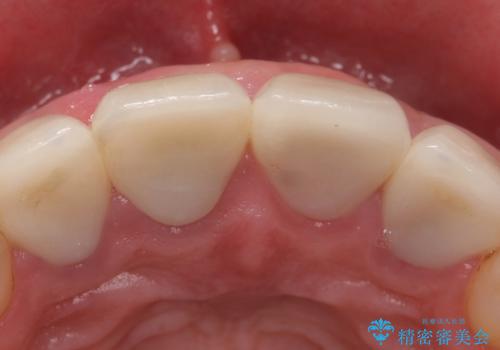

- 右上の前歯が土台ごと外れたといらっしゃった方の症例です。

ファイバーコアという土台から建て直し、咬み合わせに十分注意した上で、オールセラミッククラウンによる補綴を行いました

今回用いたオールセラミッククラウンはジルコニアフレームという白い素材の上にセラミックを盛っているため、審美性が非常に高いのが特徴です。